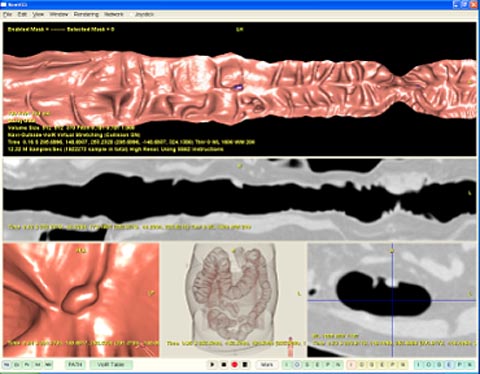

大腸の場合には、内視鏡に代わる検査としてCT画像を用いた検査法が注目されています。このような検査法はCT Colonographyと呼ばれています。CT検査で撮影される画像から仮想化内視鏡画像を生成し、その画像を基にポリープの検査を行います。しかしながら、皆さんご存知のように、大腸は曲がりくねった管状の臓器であり、仮想化内視鏡による検査では、大腸内部をフライスルーしながら腸管壁面上すると、とても時間がかかります。そこで、大腸を一直線に伸ばし切り開いた形で観察する手法が開発されてきています。また、この切り開かれた画像上に、自動的に検出された大腸ポリープ領域をマーキングすることも行われています(図1)。

図1 大腸ポリープ診断支援システムの画面例